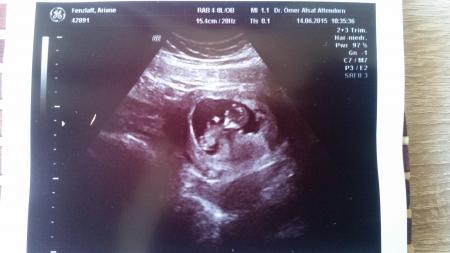

Heute war ich beim Frauenarzt.. ja ich weiß ist doch recht ungewöhnlich aufn Sonntag... war auch eher Ausnahme... mir wars recht so konnt i mein krümel wiedersehen... dieses mal hat der arzt aber leider bauchultraschall gemacht... leider sind die bilder nicht soooo schön geworden.... Was aber toll ist war das das mein krümel von rücken- liege-position auf bauchschwimmen dann auf sitz-position immer hin und her ist... war schön anzusehen... Herz ist top... schlägt kräftig Ich werd mal n bild mit ranhängen..aber wie gesagt sind leider nicht so schön dies ma...

Ne wieso das bild ist doch schön also ich kann alles erkennen :)))))

Was bilder angeht bin i schon verwöhnt... so wie bei dem wo i mitte 10.ssw war... das bild fand i toll...

Japs ich erhalte auch immer so tolle Bilder von meinen fa:)))) aber wie gesagt man kann alles sehr schön sehen;)

Wow, die Bilder sind ja schön. Meine Ärztin hat kein so tolles Gerät. Also seid froh darüber. Schön, dass es deinem kleinen Schatz gut geht.